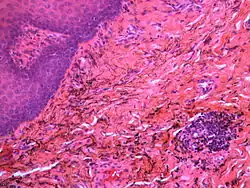

If necessary, the diagnosis can be confirmed histologically by excisional biopsy, which excludes nevi and melanomas.[3]: 138 If a biopsy is taken, the histopathologic appearance is:[1]

- Pigmented fragments of metal within connective tissue

- Staining of reticulin fibers with silver salts

- A scattered arrangement of large, dark, solid fragments or a fine, black or dark brown granules

- Large particles may be surrounded by chronically inflamed fibrous tissue

- Smaller particles surrounded by more significant inflammation, which may be granulomatous or a mixture of lymphocytes and plasma cells